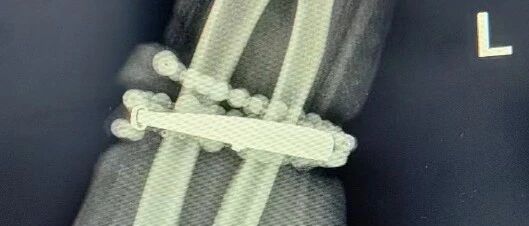

然而,就在兩周前,龔女士的情況急轉(zhuǎn)直下:手腕不僅疼痛加劇,還出現(xiàn)了明顯的紅腫,甚至有膿液滲出。她這才驚覺——手鐲和串珠,已經(jīng)有一部分“長”進(jìn)了肉里,根本取不下來了!

“這是典型的首飾長期壓迫、摩擦,加上細(xì)菌感染,引發(fā)的慢性炎癥和肉芽組織增生?!?/span>醫(yī)生介紹,此時,手鐲和串珠已經(jīng)成了一個不斷刺激皮膚、污染傷口的“病灶”,如果不盡快手術(shù)取出,感染可能進(jìn)一步擴(kuò)散,甚至危及生命或影響手臂功能。

經(jīng)過一個多小時的手術(shù),醫(yī)生們將手鐲和串珠從厚厚的增生組織中完整剝離出來。目前,龔女士恢復(fù)良好,已順利出院。